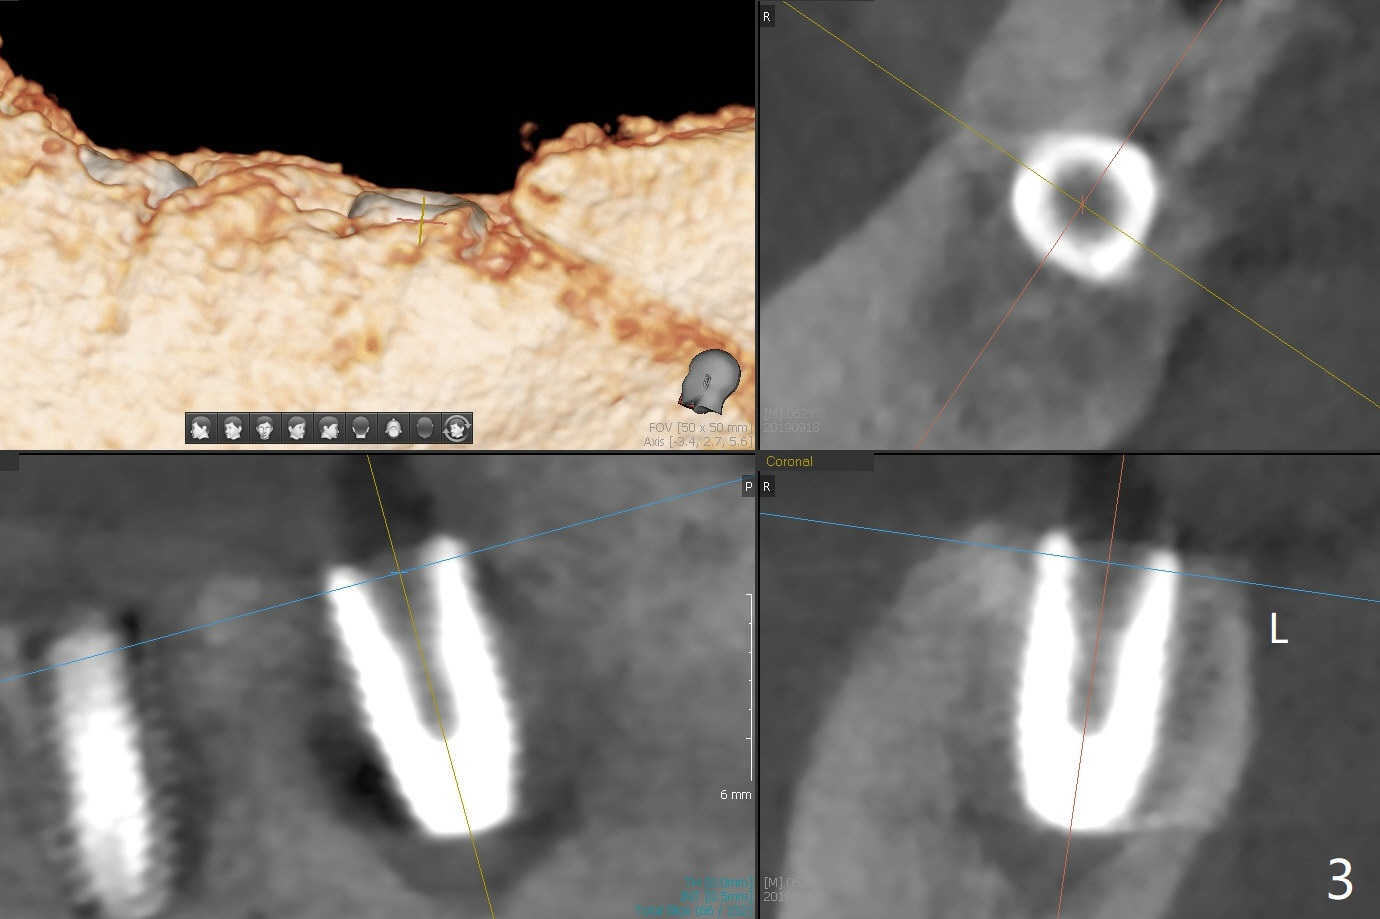

Five months post #31 implant removal with bone graft, osteotomy is initiated for a 5x10 mm implant using an existing guide. A question arises suddenly whether the bone height is reduced. Therefore a 4.5x10 mm dummy implant is placed with a fixture anchor placed at #30 (Fig.1 A). After using 4.5x8.5 mm drill with regular offset, a 5x10 mm definitive implant is placed with ~ 35 Ncm (Fig.2,3). After placement of the implant .5 mm deeper, a 8x6 mm healing abutment is placed, while the abutments return to #29 and 30 for splinted provisional (Fig.4). Two months later, the cemented abutment at #29 is loose (Fig.5) and retightened, but it remains incompletely seated for another 3 months (Fig.6). So is the one at #31 (Fig.6). After use of 4.6 and 5.6 mm bone profile drills, healing abutments are placed with apparently complete seating (Fig.7,8).